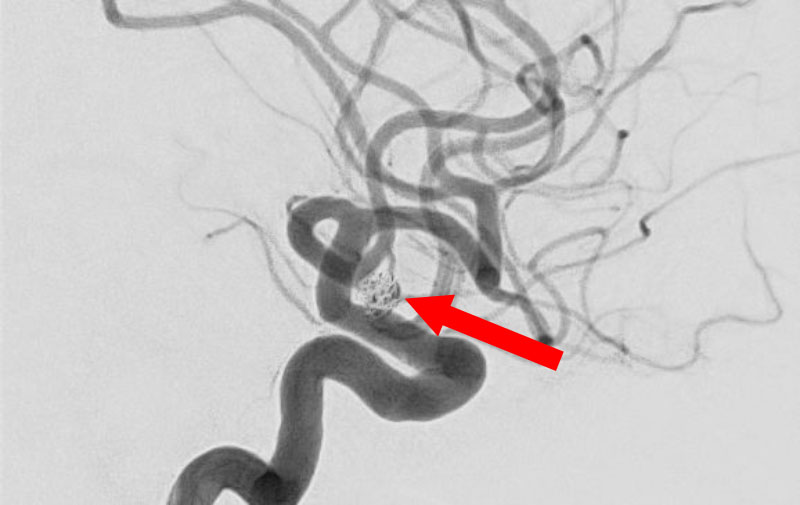

No.1596 手術後